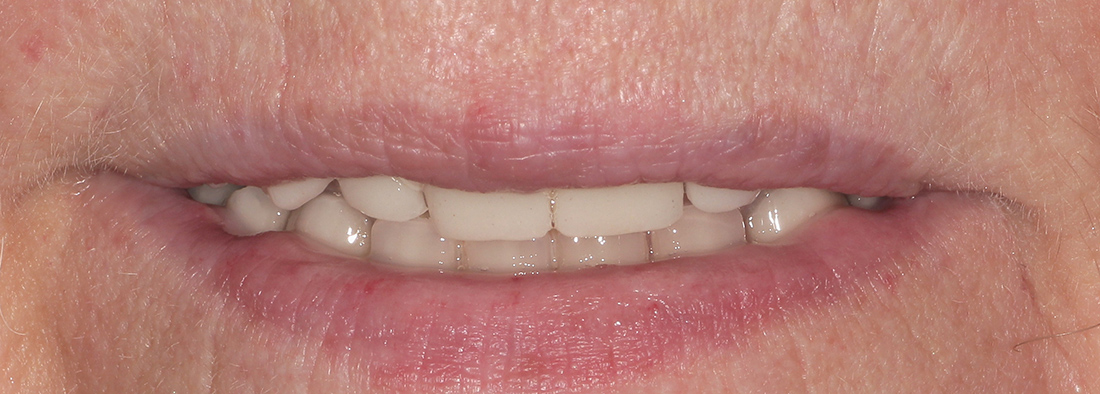

По прошествии трех месяцев пациентка была направлена на окончательное протезирование. Так за минимальный срок мы смогли избавиться от съёмного протеза и получить фиксированную конструкцию на имплантах, гораздо более удобную и функциональную.